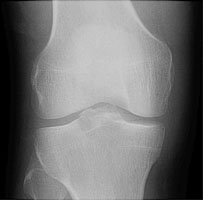

- Click on the image for a larger versionAAP radiograph of the knee. No definite fracture is seen.